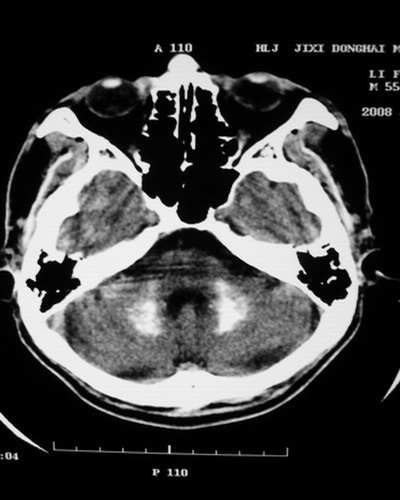

以下是引用随光逐影在2008-1-14 17:26:00的发言:[br]考虑为:甲状旁腺功能低下。需与fahr`s病相鉴别。建议:实验室检查。